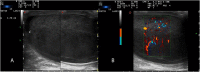

Bilateral primary testicular lymphoma